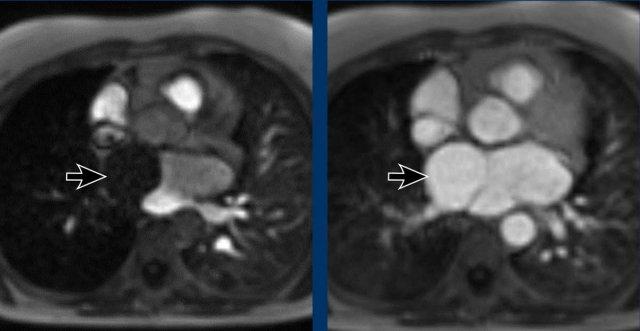

Hình ảnh

Tim ba buồng nhĩ trái (cor triatriatum sinistra) phát hiện tình cờ với hình ảnh ngấm thuốc muộn của ngăn phải nhĩ trái.

Trường hợp này ban đầu bị nhầm lẫn với huyết khối.

Tiếp tục xem hình ảnh MR…

Đây là hình ảnh MR của cùng trường hợp trên

Lấp đầy muộn của ngăn phải nhĩ trái trong tim ba buồng nhĩ trái (cor triatriatum sinistra).

Vách ngăn nhĩ trái mức độ nhẹ hơn trong tim ba buồng nhĩ, chỉ biểu hiện bằng một cấu trúc dạng dải mảnh, còn được gọi là ‘dải nhĩ trái’ (left atrial band)